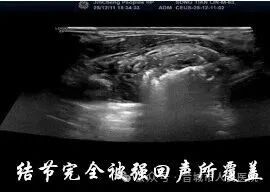

手术当天,在超声实时监控下,医生将消融针精准穿刺至结节中心。术前造影清晰勾勒出结节边界,如同 “导航定位” 一般,确保针尖精准避开正常甲状腺组织和喉返神经等关键结构。随后,消融针释放高温能量,将结节组织 “原位灭活”,整个消融过程仅用时2分34秒!

术后即时造影显示,原本高增强的结节区域已完全 “无血供”,这意味着病灶已被彻底消融。张先生的脖子上,只留下一个毫米级的针眼,按压片刻后便无明显痕迹。术后他生命体征平稳,没有出现疼痛、肿胀等不适症状,第二天就顺利出院回家。